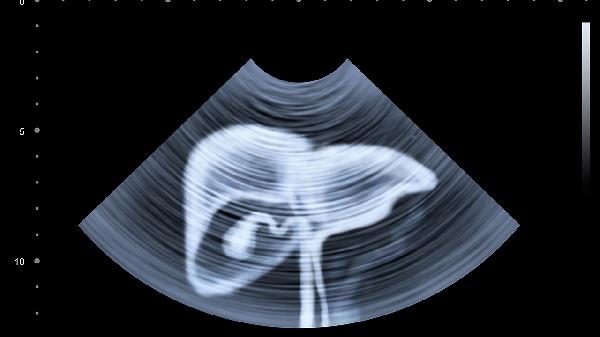

腹部B超能检查出肝脏、胆囊、胰腺、脾脏、肾脏等器官的病变,以及腹腔积液、肿块等情况。

腹部B超可以检测肝脏的大小、形态、回声特征,帮助诊断脂肪肝、肝硬化、肝囊肿、肝血管瘤等疾病。对于肝内占位性病变如肝癌,B超可作为初步筛查手段,同时能引导穿刺活检。

B超对胆囊疾病的诊断价值较高,能清晰显示胆囊结石、胆囊息肉、胆囊炎等病变。检查时可观察胆囊壁厚度、胆汁透声情况,评估胆囊收缩功能。

通过B超能发现胰腺肿大、胰管扩张等异常,辅助诊断急性胰腺炎、慢性胰腺炎。对于胰腺囊肿、胰腺肿瘤等占位性病变有一定筛查作用,但受肠道气体干扰时检出率可能下降。